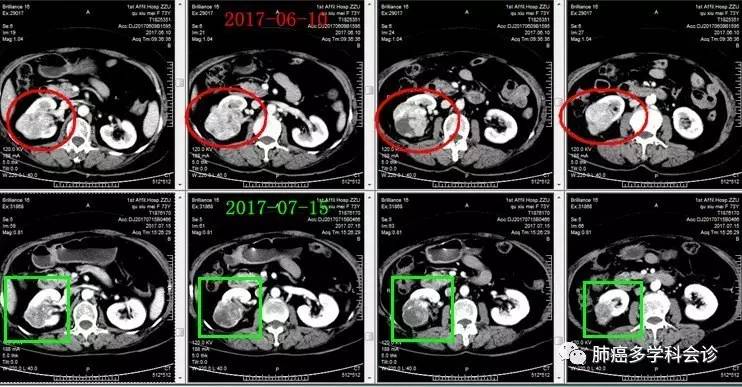

微信图片_20170721110259.jpg诊断为“肾癌多发转移”,阿昔替尼 5mg 每天 2 次连续口服 1 月后,复查CT:右肾肿块明显缩小,双肺转移灶也明显缩小或消失。微信图片_20170721110302.jpg